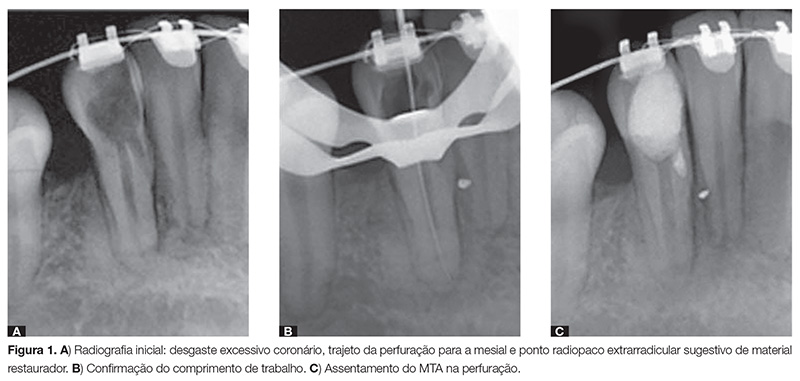

Ao se realizar o exame radiográfico periapical intrabucal do dente 43, foi evidenciado um desgaste excessivo na abertura e na porção cervical. Por mesial era possível ver o trajeto da perfuração. A imagem também apresentava um ponto radiopaco, extrarradicular, sugestivo de algum tipo de material restaurador (Fig. 1A). Após realização de todos os testes e exames clínicos, o diagnóstico clínico provável era de necrose pulpar.

Durante o preparo biomecânico do canal radicular, foi realizada a odontometria de confirmação do comprimento de trabalho e realização da patência apical (Fig. 1B). Após o preparo biomecânico do canal radicular, esse foi seco com pontas de papel estéreis e, então, foi inundado com EDTA trissódico 17% por 3 minutos, com agitação manual para melhor limpeza do canal. Após esse período, o EDTA foi removido e nova irrigação com hipoclorito de sódio foi realizada, seguida de nova secagem do canal radicular. Na sequência, houve a aplicação de uma medicação intracanal à base de pasta de hidróxido de cálcio com propilenoglicol, a fim de auxiliar na descontaminação do canal radicular e da perfuração.

Passados 15 dias, a medicação intracanal foi removida com a finalidade de promover o fechamento da perfuração. O material escolhido para fazer o fechamento definitivo da perfuração foi o MTA branco da marca Angelus, que foi manipulado conforme indicação do fabricante. A inserção do MTA na perfuração foi feita com calcadores tipo Paiva, e o assentamento final do mesmo foi realizado com bolinhas de algodão umedecidas em água destilada. O MTA foi inserido na perfuração com auxílio de microscópio e sem exercer muita pressão para evitar que extravasasse para o ligamento periodontal.

Realizou-se tomada radiográfica periapical intrabucal para verificar o assentamento do MTA na perfuração. Foi possível observar radiograficamente que não houve extravasamento para a região do ligamento periodontal, descartando momentaneamente a intervenção cirúrgica para o caso (Fig. 1C).